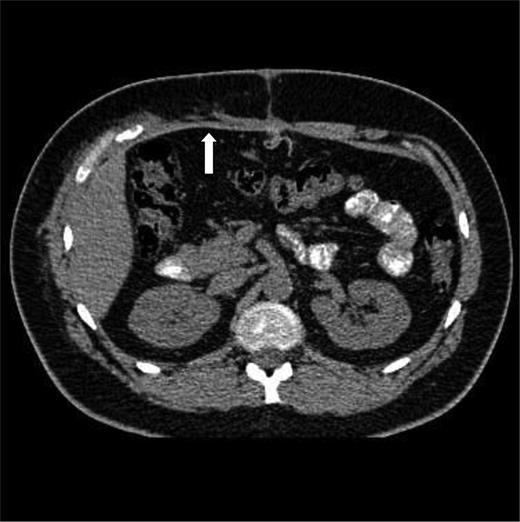

Trauma series computed tomography (CT) scans demonstrated a flail segment between the sixth and eight ribs with disruption of the intercostal muscles and a small right haemothorax (Fig. 1a). In the abdomen, there was hepatic contusion with an intrinsic liver injury (Fig. 1b). Blood was noted around the liver with minor active haemorrhage. The right abdominal wall was ruptured—the right rectus abdominis muscle had been torn from its costal attachments to the midpoint. The hepatic flexure of the colon had herniated through the intercostal muscles of the eighth and ninth ribs and was lying adjacent to the fractured ribs (Fig. 1c). Both small and large bowel had herniated through the abdominal wall lateral to rectus abdominis, but remained covered by external oblique (Fig. 1d). Herniation of small and large bowel immediately adjacent to the fractured ribs raised the suspicion of occult bowel injury not detected on CT.

(a–d) Initial CT imaging performed as part of the secondary survey.